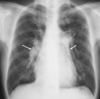

Estudios de imagen para Enfermedad Pulmonar Infiltrativa Difusa Crónica

RX * Poco específica * Patrón intersticial bibasal TC * Diagnóstico de NIU * “Patrón en panal” * Bronquiectasias por tracción en las bases (dilatación bronquial)

80

Patrón en panal

81

Patrón intersticial bibasal

82